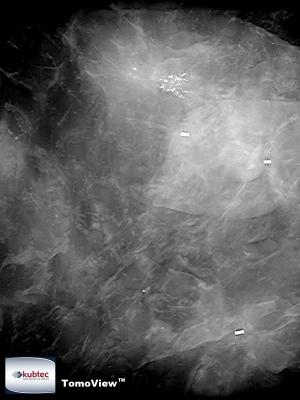

An image taken with the TomoView, Mozart, new technology.

Kubtec, a leader in innovation for digital specimen radiography, announced its development of TomoView, a groundbreaking tomosynthesis technology for digital specimen radiography of excised breast tissue. The company’s patent-pending technology allows for multi-planar x-ray imaging for thorough margin analysis of excised breast tissue and is the core foundation on which Kubtec’s upcoming system release, MOZART, is based.

By employing Kubtec’s advanced TomoView technology, MOZART will offer a comprehensive solution for imaging excised breast tissue while increasing accuracy, saving time, and reducing re-excision rates in the operating room.

“The TomoView technology in MOZART allows for comprehensive intraoperative margin analysis in a single step, without turning and repositioning the specimen container multiple times to obtain additional views,” said Kubtec’s Director of Research and Development, Chester Lowe, Ph.D., FACR. “Using TomoView’s multi-dimensional imaging technology, and requiring no repositioning of specimens, the MOZART system will provide a faster, more efficient specimen radiography solution for radiology, surgery, and pathology department.”